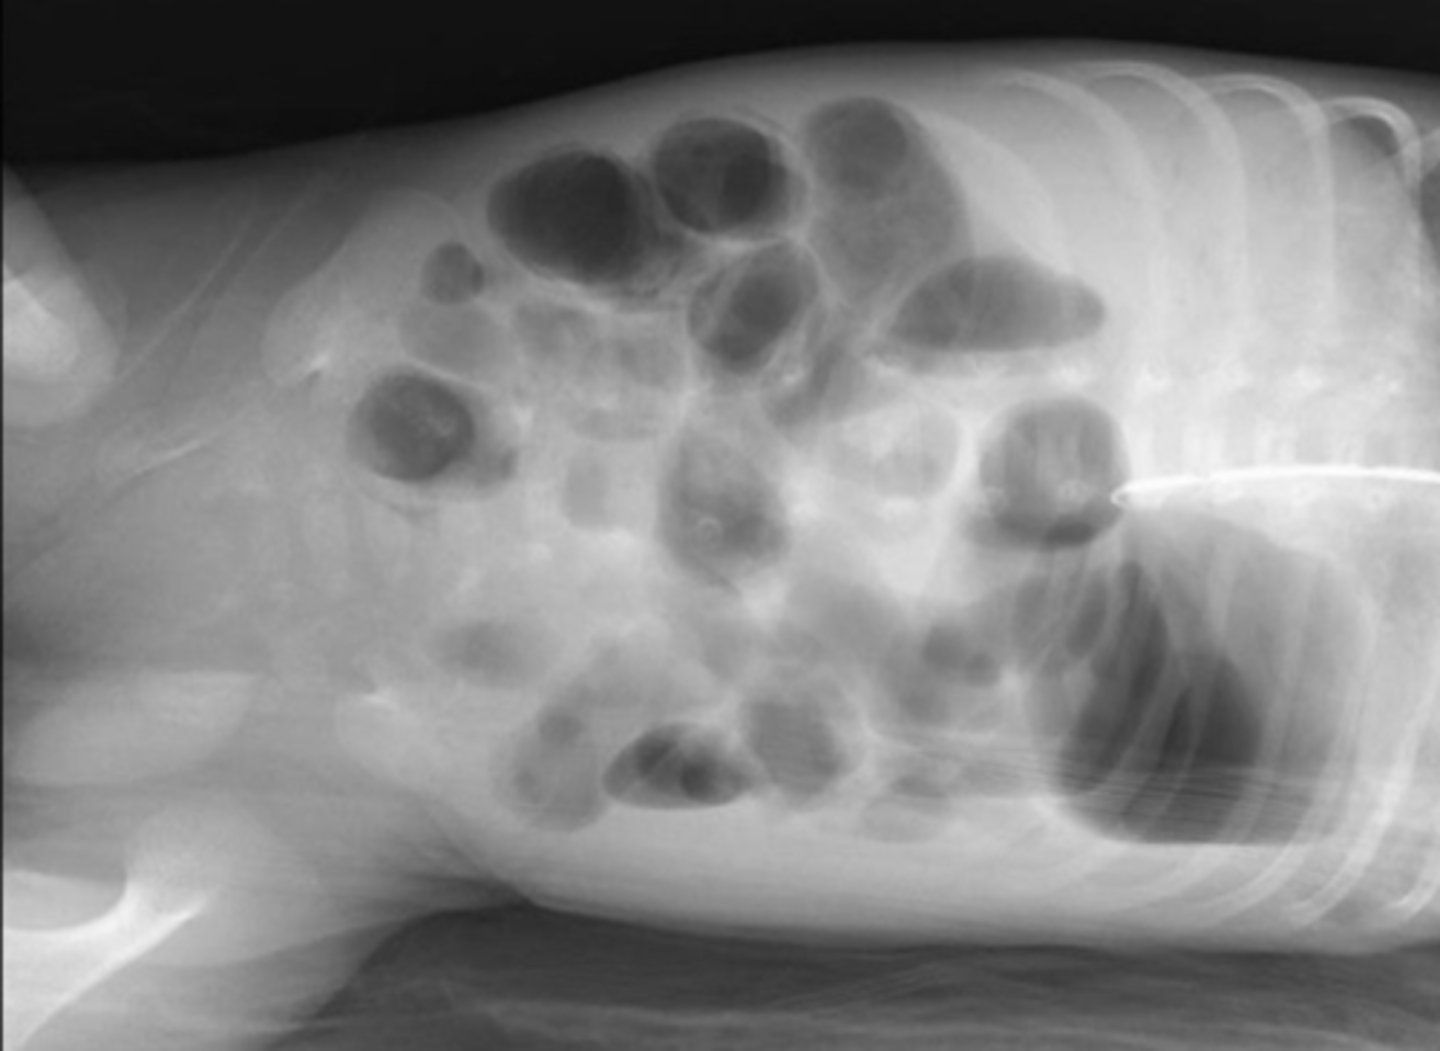

Intramural air because of necrotizing enterocolitis (NEC)

dilated loops of bowel air fluid levels

dilated loops of bowel